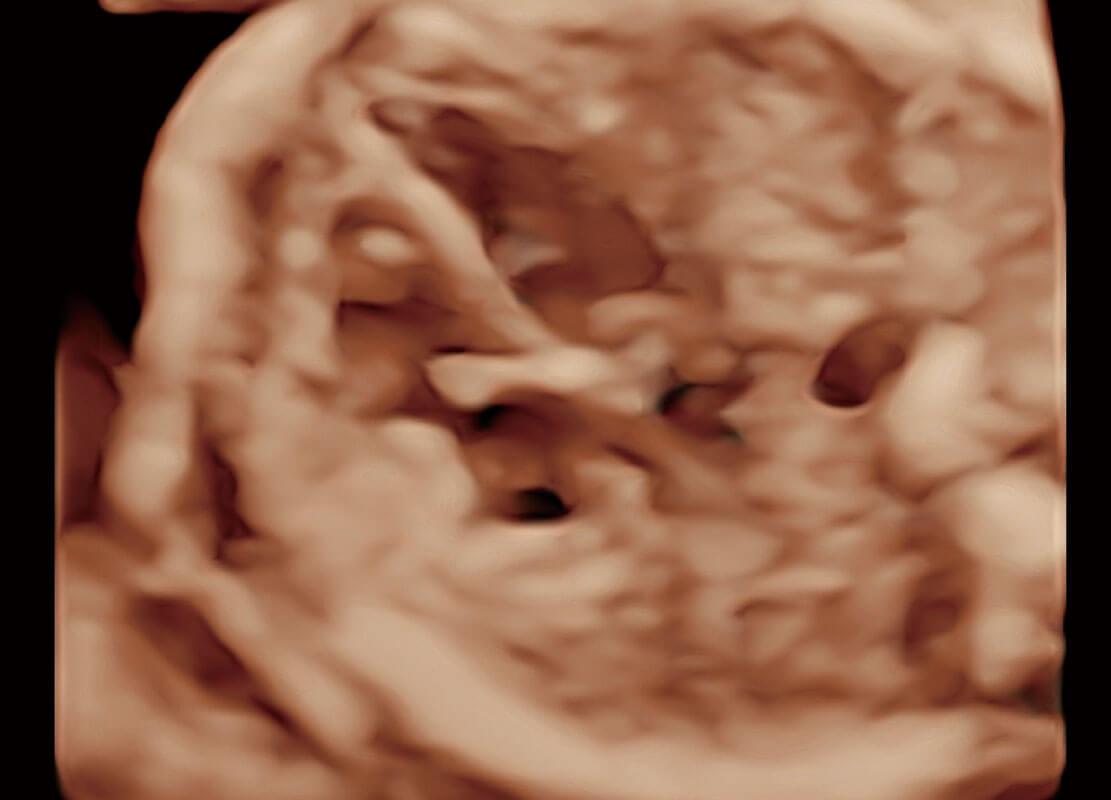

腔內(nèi)三維-宮內(nèi)節(jié)育器

腔內(nèi)三維-光影成像